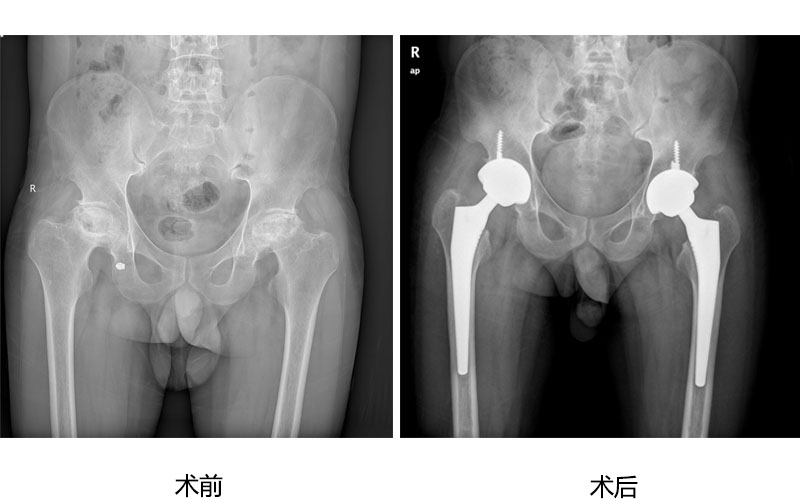

人工关节置换

人工关节置换为广大高龄老年股骨颈骨折、股骨粗隆间骨折病人提供快速康复治疗,为严重股骨头坏死、膝关节炎病人解除病痛,恢复正常行走功能。 病例展示如下:

老年股骨颈骨折微创全髋人工关节置换术

高龄股骨粗隆间骨折半髋人工关节置换术

股骨头坏死微创全髋人工关节置换术

老年膝骨性关节炎人工膝关节置换术